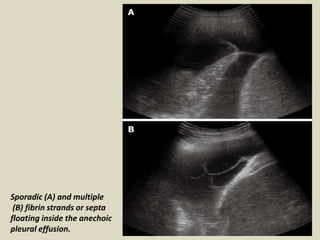

Abdominal abnormalities identified on ultrasound. The success rate is low when the effusion is loculated and septated. About Press Copyright Contact us Creators Advertise Developers Terms Privacy Policy Safety How YouTube works Test new features Press Copyright Contact us Creators.

Massive Left Sided Pleural Effusion With Floating Fibrin Deposition Download Scientific Diagram

Different Types Of Pleural Effusion On Ultrasound Scan A Exudate B Download Scientific Diagram